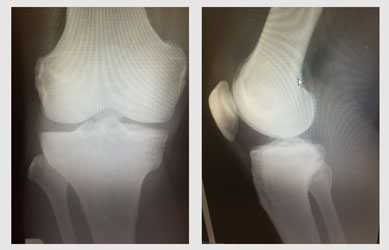

変形の重症度と痛みは関係がある

これは変形性膝関節症の「重症度」を示す指標です。 感覚的にはもちろん「変形がひどければひどいほど痛みが強い」と考えがちですが、実は

変形と痛みには関連がない

という研究結果が多数報告されています。

他にも

・40歳以上の「無症状の膝」でも、37%に変形がみられる

・Grade4(重症)の膝でも、30%は無症状である

というエビデンスも多数存在します。

つまり、いくら膝の変形が重度であったとしても

症状の改善を諦める必要はないのです。